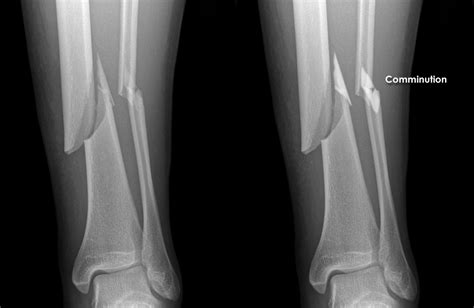

• Fracture Pattern: This refers to the shape or type of the break. There are several fracture patterns, including transverse (a straight, horizontal break), oblique (a break that runs diagonally), spiral (a break that twists around the bone, often caused by a twisting force), and comminuted (where the bone is broken into multiple pieces). Comminuted fractures are generally more complex to treat. Knowing the fracture pattern helps the surgeon understand the mechanism of injury (how the break happened) and helps them make a good treatment plan.